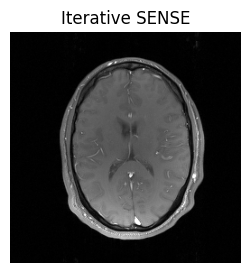

As expected, we still see undersampling artifacts in the image. In order to get rid of them, we try can a more sophisticated reconstruction method, such as the iterative SENSE algorithm. As you might have guessed, these are also included in MRpro: Instead of the DirectReconstruction, we can use IterativeSENSEReconstruction:

sense_recon_us = mrpro.algorithms.reconstruction.IterativeSENSEReconstruction(

kdata_us,

csm=direct_recon_calib_lines.csm_op,

n_iterations=8,

)

idat_us_sense = sense_recon_us(kdata_us)

show_images(idat_us_sense.rss().squeeze(), titles=['Iterative SENSE'])

../_images/148912193a844453c6ebdcab1cccfcbb0c56c04e1c7cefa8e9d4f58ee9b3938d.png

This looks better! More information about the iterative SENSE reconstruction and its implementation in MRpro can be found in the examples Iterative SENSE reconstruction of 2D golden angle radial data and Regularized iterative SENSE reconstruction of 2D golden angle radial data.